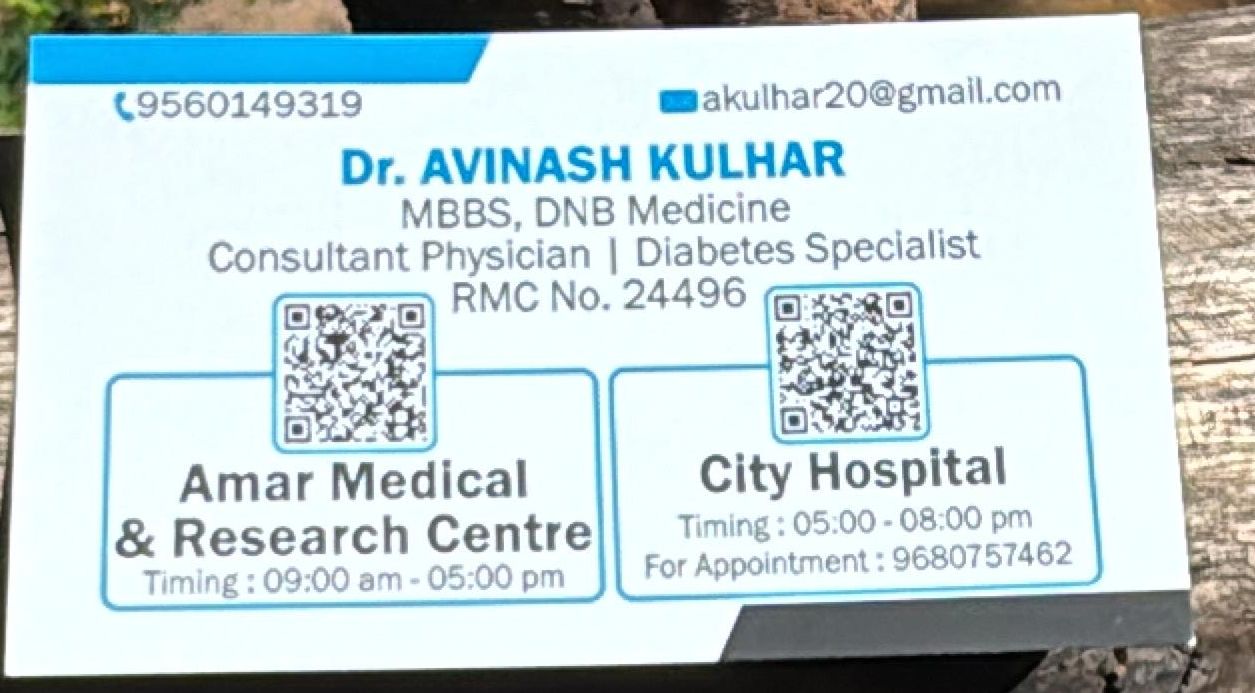

Dr. Avinash Kulhar (Consultant Physician in Jaipur)

Dr. Avinash Kulhar is a distinguished General Physician and Diabetes Expert in Jaipur, known for his expertise in diagnosing and managing a wide range of medical conditions. His compassionate approach and dedication to patient care have earned him a trusted reputation in the healthcare community.

With extensive experience in the medical field, Dr. Kulhar combines his knowledge and skills to provide personalized treatment plans for his patients. His commitment to improving health outcomes is reflected in his role as a dedicated consultant, ensuring comprehensive care for individuals with both common and complex health concerns.

In addition to his hospital responsibilities, Dr. Avinash Kulhar extends his expertise to the community through his dedicated clinic in Jothwada, Jaipur. Patients visiting his clinic receive personalized care, where compassion and understanding are at the core of his treatment approach.

Dr. Avinash Kulhar has earned immense trust and respect from his patients and peers due to his unwavering commitment to delivering exceptional medical care. His dedication to continuous learning and enhancing healthcare services reflects his mission to improve patient outcomes.

Beyond his clinical practice, Dr. Avinash Kulhar remains deeply invested in his patients' well-being, offering not only medical solutions but also emotional support during challenging times. His comprehensive approach to healthcare emphasizes treating patients with empathy and care.

For those seeking a compassionate and skilled healthcare provider, Dr. Avinash Kulhar stands as a beacon of trust and reliability. His contributions to the medical community and his steadfast dedication to patient care make him a valued figure in Jaipur's healthcare landscape.

Qualifications:

MBBS, MD (Medicine), PG Diploma in Diabetology

Experience:

Over 15 years in diagnosing and managing complex medical conditions

Specialties:

Diabetes Management, Hypertension, Thyroid Disorders, and General Health Checkups